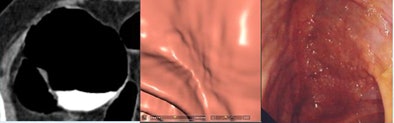

![]() |

| Two low-grade dysplastic polyps < 1 mm in height, including a "carpet" lesion, were not detected by CAD or initially at CTC (left, middle), but were later found at CTC and conventional colonoscopy (right). All images courtesy of Dr. Franco Iafrate. |

Two lesions < 1 mm in height were not detected by either CAD or the radiologists, but were found at conventional colonoscopy. Both could be seen retrospectively at CTC as a focal wall thickening.